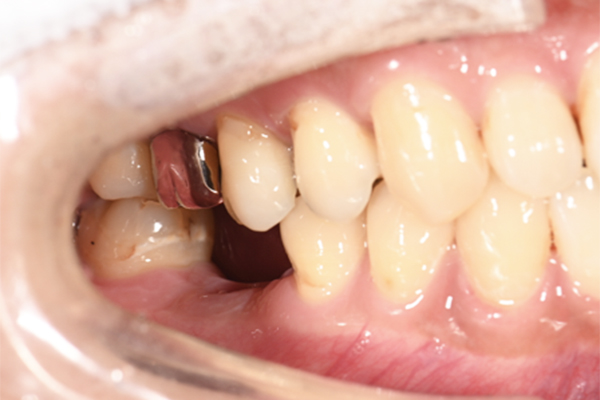

| 主訴 | 右下の奥歯が痛い |

|---|---|

| 治療内容 | 右下奥歯が割れていたため抜歯、その後インプラント治療を行った。(左の写真は抜歯後の写真) |

| 治療期間 | 4ヶ月 |

| 治療費 | 41万5千円 |

| 治療 リスク | 抜歯後インプラントの処置まで3ヶ月程度治癒期間(骨ができるまでの期間)が必要なことがあります。 |